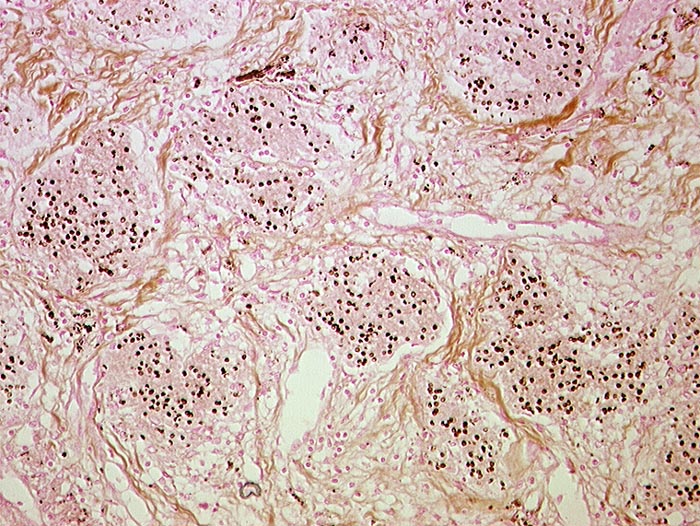

Bei Pneumocystis carinii handelt es sich um eine Pilzinfektion. Die Organismen sind in intraalveolärem schaumigem Material nachweisbar. Dieses flockig-schaumige Material färbt sich in der Papanicolaou Färbung eosinophil oder basophil. Die Erreger selbst sind in der Papanicolaou Färbung nur schlecht sichtbar. Die Zysten lassen sich aber mit der Grocott-Versilberung darstellen. Sie sind 4 bis 8 Mikrometer gross, rundoval und enthalten einen zentralen schwarzen Punkt. Die Zysten enthalten bis zu acht 0.5 bis 1 Mikrometer messende Trophozoiten.